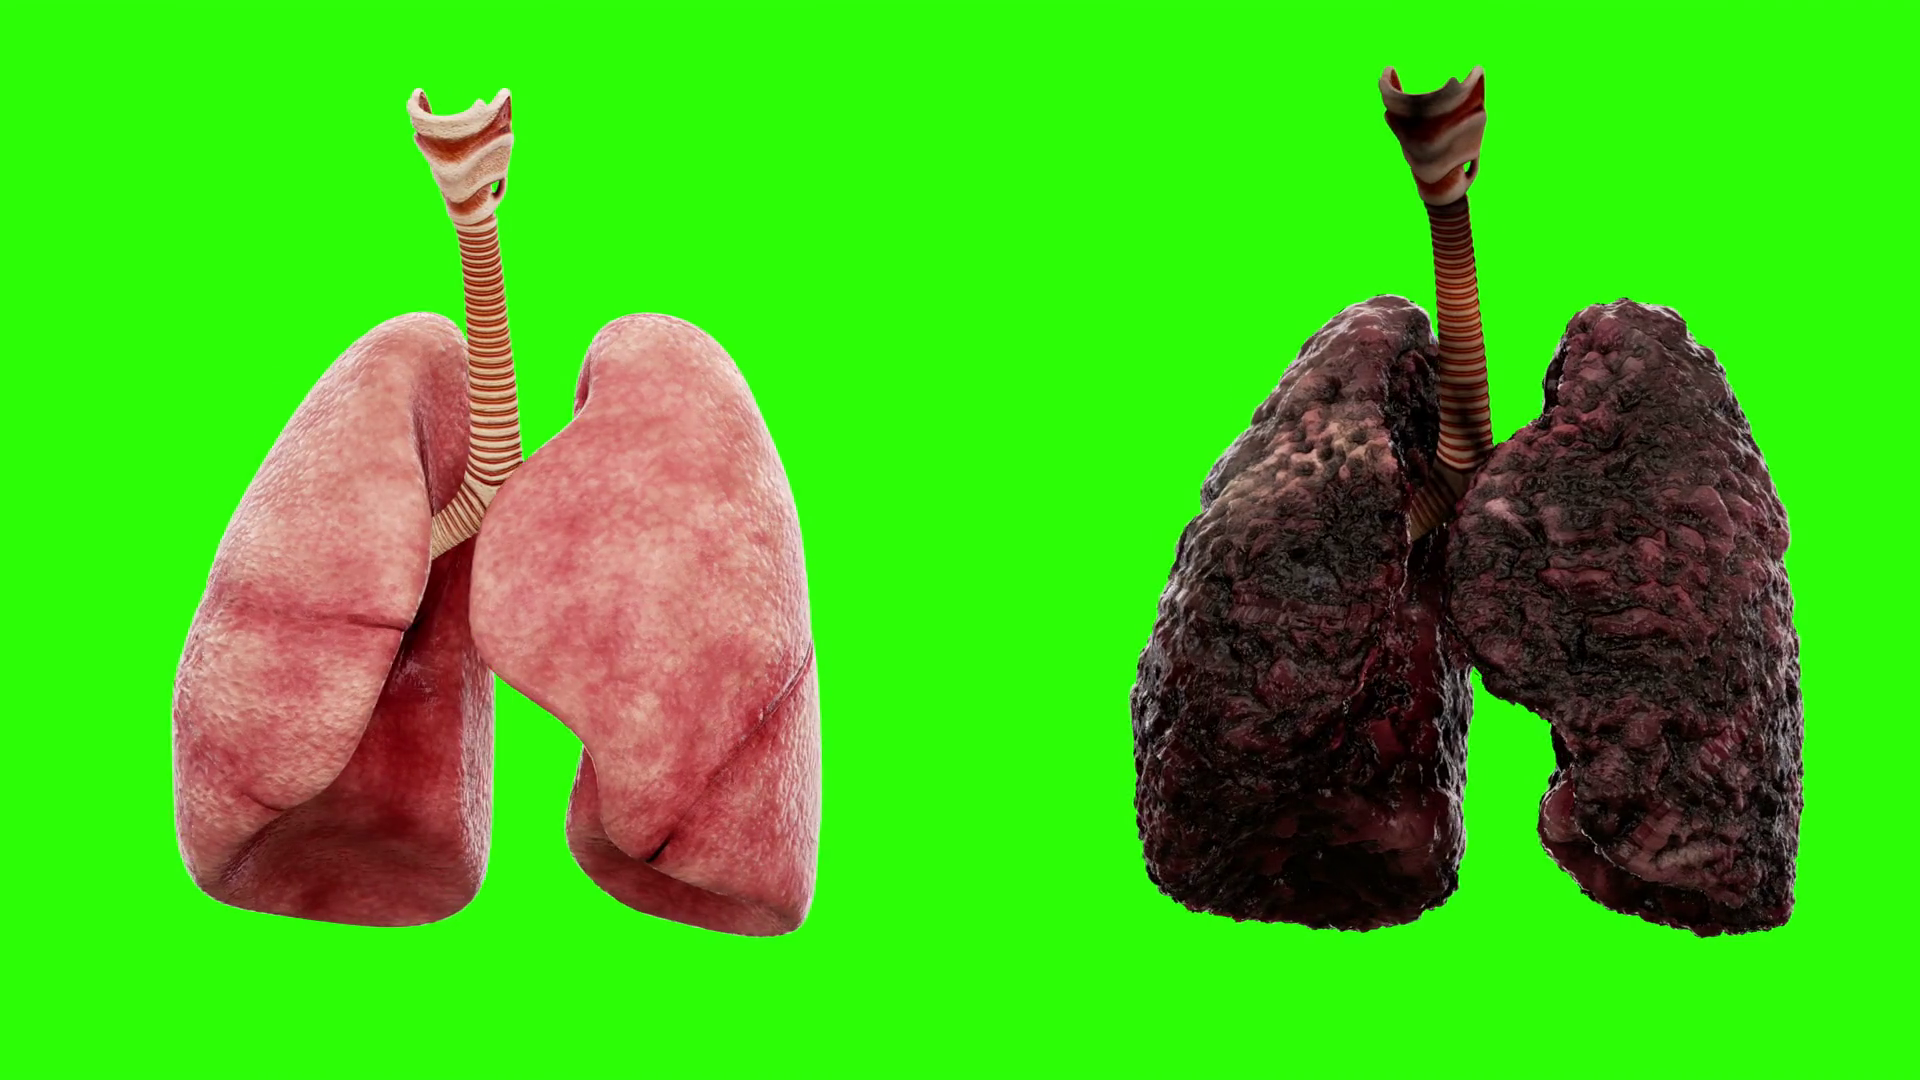

Здоровые Легкие Картинки

Здоровые Легкие Картинки 117 фото